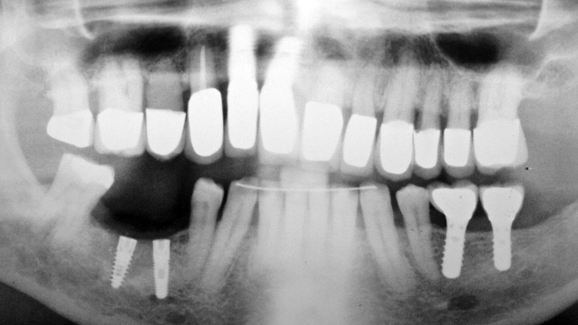

A 60-year-old male patient reported to our office for restoration of two implants placed in regions 29 and 30 three months earlier at a different office (Fig. 1).

According to the records obtained from the previous treating dentist, a surgical guide was not used when placing the implants.

Implant 29 had been placed at an inadequate angle. Owing to the angulation of the implant, the simultaneous placement of two impression posts was not possible, rendering it impossible to take an impression (Fig. 2).

Since the implant was placed in proximity to the inferior alveolar nerve, removal of the integrated implant was not advisable.